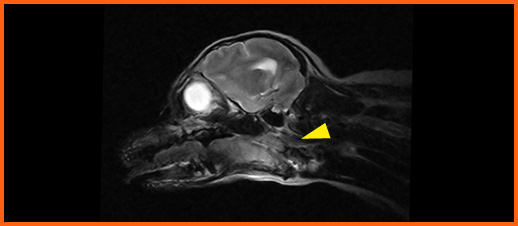

We offer general medical and surgical services with advanced diagnostic facilities. Also, we are one of the few clinics in Hong Kong that provide both CT Scan and MRI services for animals. Our team are equipped to provide detail nursing care for hospitalize pets.